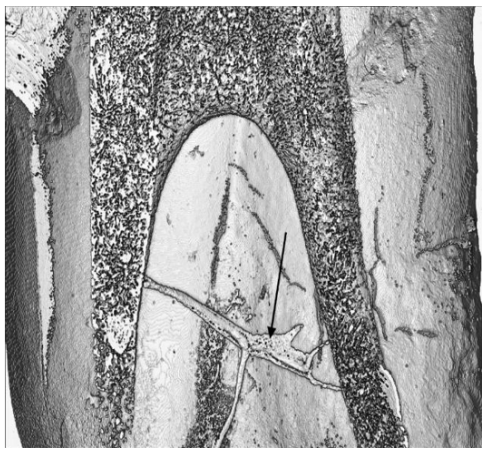

We can see, if we will to see, that the distinctions disinfection, antispetics, obturation are not even close to sterilization and that is our dilemma in the profession. No one has addressed this issue, but I do here, in this document. Our colleagues insist that they can sterilize and obturate the radiculary anatomy of the canals of Odontons. I challenge them to obturate and sterilize the one we see in (Figure 1). This is a photo micro- graph from” EndoCal 10 Obturation Voids in Root Canal and Isthmus of a Human Premolar: A Synchrotron micro-CT Imaging Study [4].

The voids seen at A, B, and C are only of a fraction of the accessory canals in this premolar, not to mention the billion and billions of dental tubules that transect the sterile root structure from pulp chamber to peripheral cementum/periodontium/bone hematopoetic tissues. The presence of pulp tissue is still seen in C. Micro- organisms were not retrieved in this study, but neither was there an attempt to retrieve. The purpose of the study was the obturation effectiveness of EndoCal 10, which they concluded was as good as gutta-percha. (Ho-Hum!) At the level of about 3 microns in diameter the canals in human Odontons are superhighways or vast oceans to fill with sealants used in root canal therapy. And we find huge voids in the filling material of Root Canal systems as well as voids in the canals that and not able to be penetrated with sealants.

The study on obturation concluded the following regarding (Figure 2), the isthmus between the premolars two roots, left and right:

- “The isthmus (see arrow Figure 2) is a continuous one connecting both root canals, and accordingly can be classified as a type V isthmus as defined in the literature (Hsu & Kim 1998).

- Some 2D and 3D images showed remnants of pulp tissue inside the isthmus.

- The isthmus was partially obturated and Endocal 10 was able to flow to a certain extent from one end as shown in the series of images in Figure 2

- This is an indication that no hard debris resulting from the preparation of the root canals plugged the isthmus.

- Through 3D visualization, we observed that the geometry of the isthmus is tubular in structure. It is narrow at the root canal connecting ends and has dead-end branches emerging from it. The isthmus’ diameter increases to a maximum in between its two ends, which causes a pressure drop in the Endocal’s flow through it. The pressure drop is an impeding factor to the flow of Endocal 10 through the isthmus.

- As shown in (Figures 1 & 2) the isthmus is slanted downwards from the left root canal to the right one. Accordingly, it was easier for the EndoCal to flow downwards and partially obturate the isthmus at the left end, rather than flow upwards at the right end.”